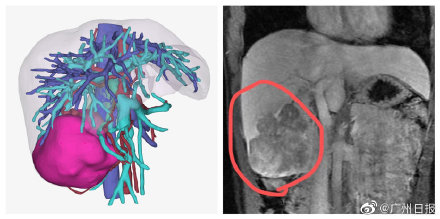

醫生表示,“慢乙肝”患者本身具備肝癌高風險,加之小黎長期有不良作息和生活習慣,導致了這麼嚴重的結果。幸好,小黎身體狀況不錯,腫瘤沒有侵犯臨近器官,也沒有遠處轉移,醫生最終為她做了右半肝切除手術,切除腫瘤,術後小黎恢復良好。(廣州日報·新花城記者:軒慧)